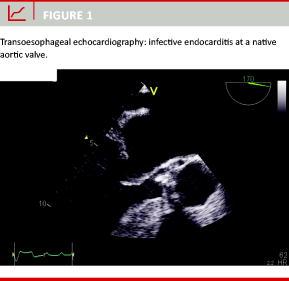

Table 2 lists the affected valves and the related outcome. Transthoracic echocardiography (TTE) and/or transoesophageal echocardiography (TOE) revealed clear signs of IE in 118 patients (78%) (Figure 1). Remarkably, four out of 34 patients with a prosthetic valve had IE at their native valve.